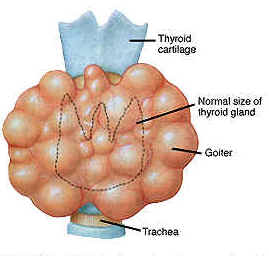

Tag: ipotiroidismo

Nuove intuizioni sull’ipotiroidismo

Un team di ricerca internazionale della Rush University Medical Center, ha acquisito nuove importanti infomazioni sull’ipotiroidismo che possono portare allo…